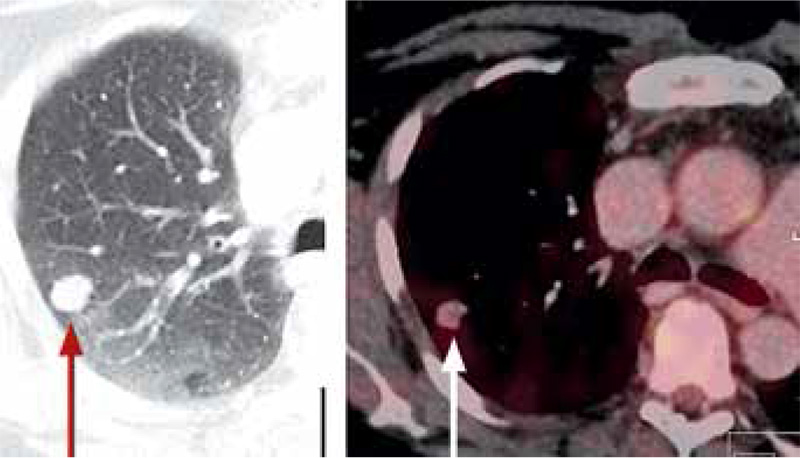

Ytterligare diagnostik behövdes för 21 av de 58 patienterna med lungcancer, vanligen för att bekräfta cancerdiagnosen i tveksamt operabla fall eller där riktad strålbehandling (i regel med transtorakal punktion) övervägdes (nio fall) eller för att utesluta eller konfirmera spridd sjukdom. Sensitiviteten för cancer var hög vid PET/DT. Endast en av de 63 maligniteterna bedömdes vara negativ (Tabell I, Figur 1). Spridd sjukdom (stadium 4) kunde påvisas hos 17 patienter.

Den vanligaste metastaslokalen var skelettet, där flertalet patienter saknade lokala symtom (Figur 2 och 3). Engagemang av regionala lymf­körtlar påvisades också i många fall. Tre fall av tidigare ej känd synkron tumör påvisades: bröstcancer, prostatacancer respektive rektalcancer. Falskt positiva fynd förekom också vid t ex infektioner.

Figur 3. Ockult skelettmetastas vid rutinmässig PET/DT-undersökning.